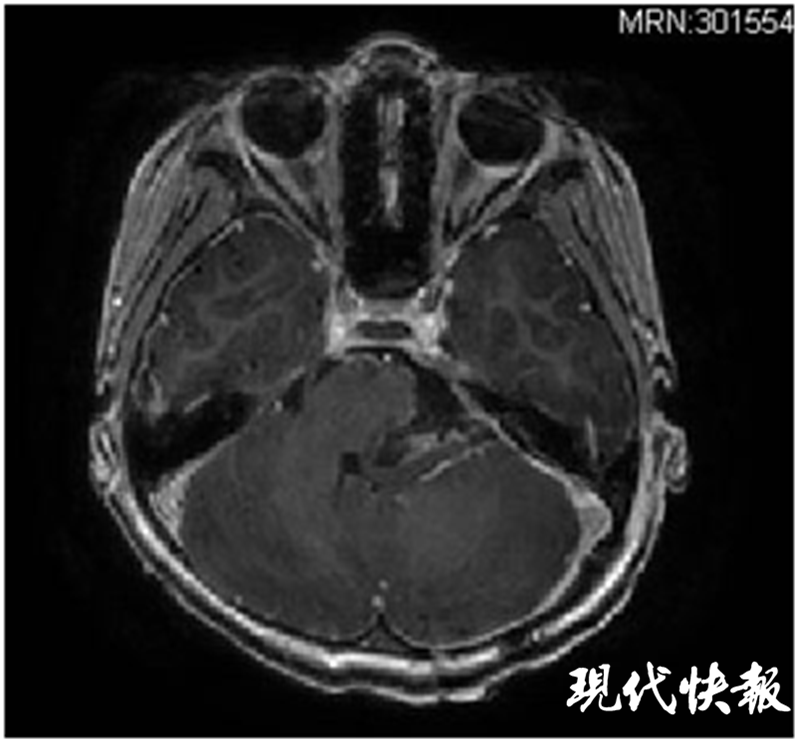

△術(shù)后核磁共振顯示腫瘤全切,腦干復(fù)位

手術(shù)團(tuán)隊(duì)在術(shù)前反復(fù)討論,制定了最佳的手術(shù)方案,并對手術(shù)中可能出現(xiàn)的各種緊急狀況做了充分準(zhǔn)備。麻醉師、護(hù)士時刻監(jiān)測,保證了患兒生命體征始終平穩(wěn)。最終,歷時6個多小時的手術(shù),不但成功將諾諾腦內(nèi)的腫瘤完全切除,而且保留了腫瘤周圍所有正常的血管和神經(jīng)。

術(shù)后經(jīng)過一段時間調(diào)理,諾諾很快就能下地活動,頭痛和嘔吐的癥狀也都消失了。